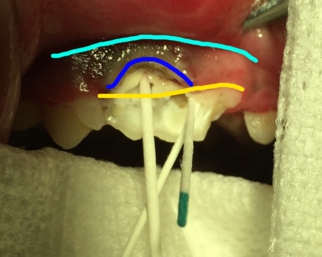

では実際の症例を見てみましょう。

…

まず、黄色いラインは実際の歯肉のラインを示しております。青のラインはレーザーを使用して歯肉を切り上げたラインを示しております。水色のラインは歯肉粘粘膜境界部であり、切り上げることのできる最大の位置(一番上)を示しております。

術後の写真になります。